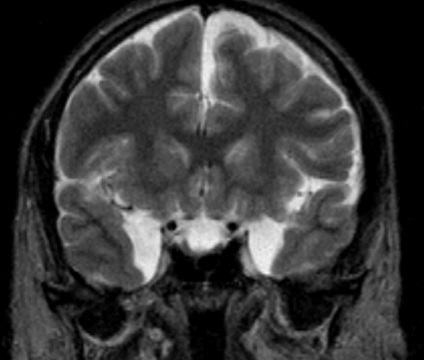

Cele mai multe tumori de acest tip, în cazul în care acestea sunt boli congenitale și creșterea în dimensiune pe o perioadă lungă de timp, medicii recomandă să nu pentru a elimina chirurgical, dar planificat să-și petreacă cursul conservator de tratament și pentru a monitoriza dimensiunea chistului arahnoidici a lobului temporal stâng. controlul tumorii profilactică în acest caz, se produce anual folosind RMN sau CT-scan a zonelor cu probleme și țesuturile înconjurătoare.